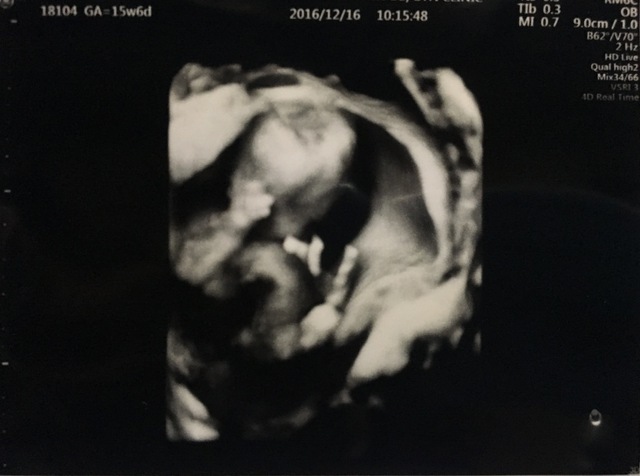

15週3日(15w3d・男の子)|kaaaa さん(25歳)

エコー写真撮影時のエピソード:

第二子にして初めて4Dエコーを貰った時のものです。まだ4ヶ月で胎動もなく今まで3Dエコーではぼんやりとした輪郭しか分からなかったのにちゃんと人の形になってる!!と感動しました。

主人も今まではエコーを見ても「ふーん」ぐらいの素っ気ない返事でしたが、これには喜んでくれました!やっぱり見やすい方が実感湧くのでしょうか。(笑)

上の子もまだ1歳でしたが、この頃から「ママのお腹には赤ちゃんがいるんだよ~~。こんなして寝んねしてるよ~~。」と話していました。毎日お腹をさすってくれて産まれる前からお姉ちゃんをしてくれています。